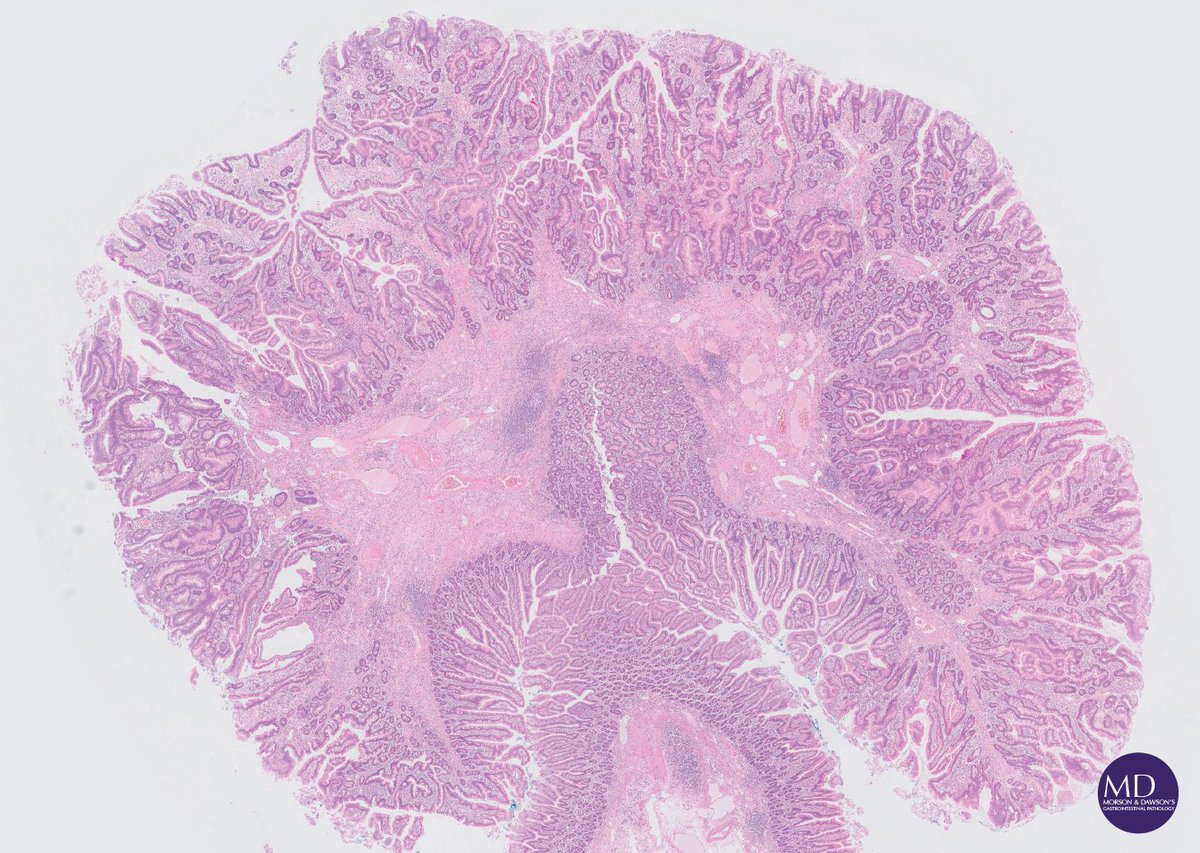

@MD_GIPath

Morson GI pathology

8 years

Clean sweep in a young patient with Cowden's syndrome (PTEN-mutation documented), polyps from all major GI sites reveals the syndrome's phenotypic heterogeneity @DraEosina @RhondaYantiss @abobbyandrews @gordon_hutchins